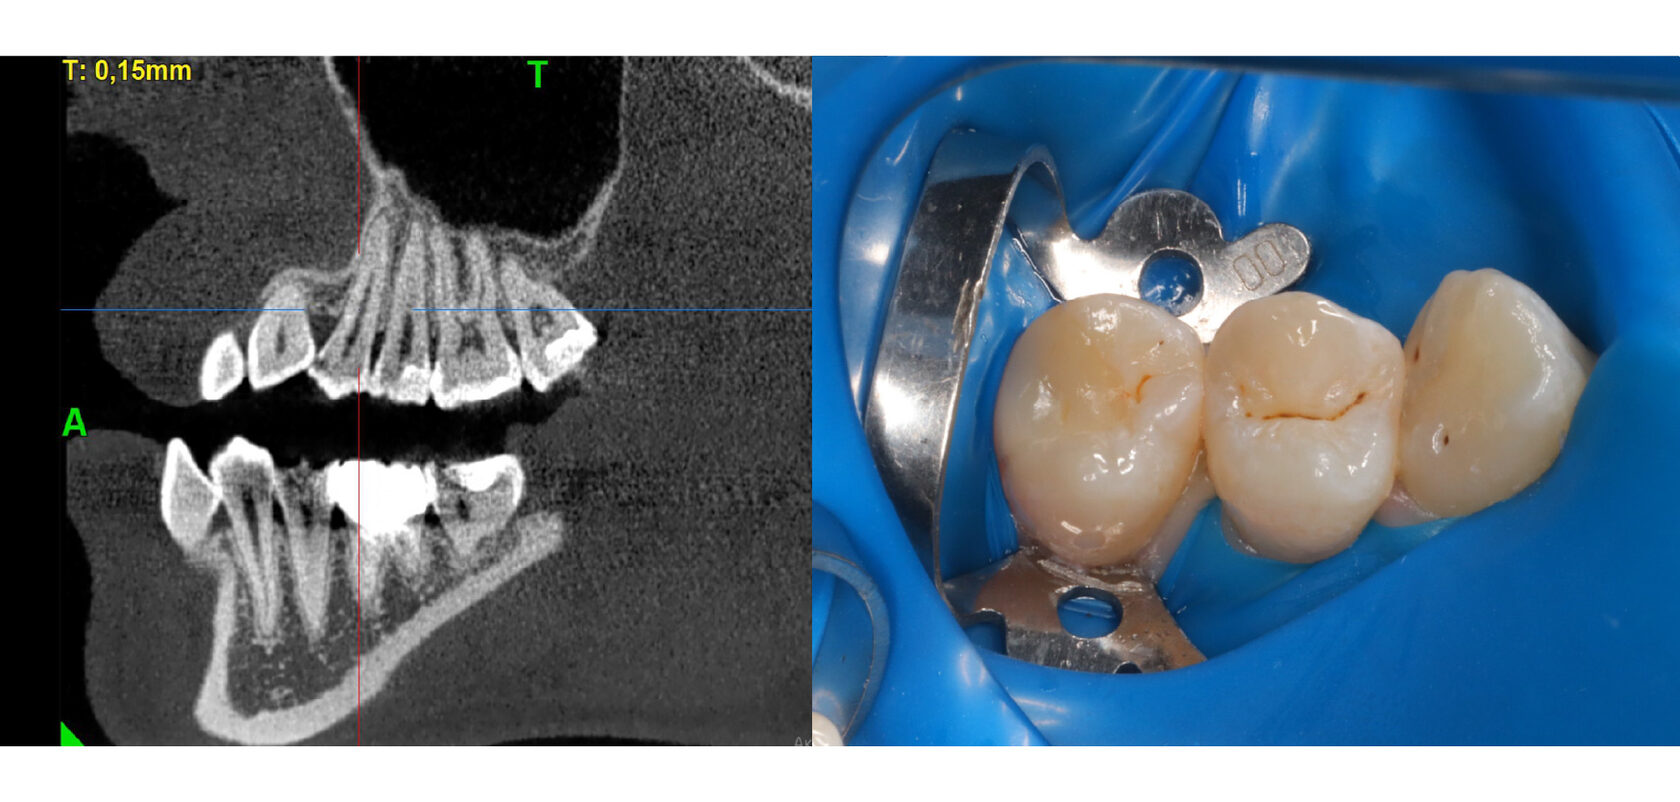

С этим и встретился наш пациент. Жалоб нет. Обратился профилактически и на компьютерной томографии была обнаружена достаточно большой кариес, хотя в полости рта ничего не видно.

Случай достаточно классический, но осложнен расположением соседнего зуба, клыка. он развернулся на 45 градусов, поэтому мешает и пациенту, качественно прочистить зуб, и врачу в лечении.